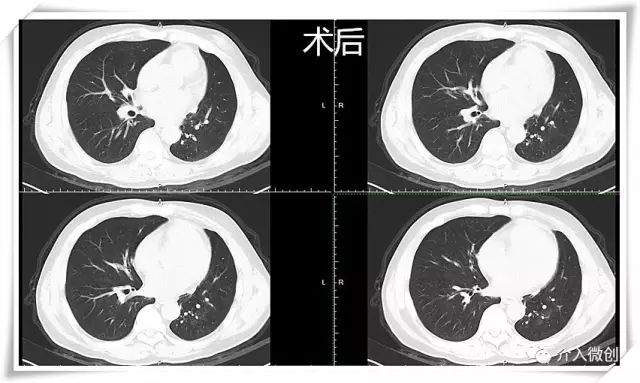

例2:左肺小细胞肺癌放化疗后进展

中年男性患者,左肺小细胞肺癌(局限期),经过EP方案化疗7周期,期间配合同步左肺及纵隔病灶外放疗。治疗后期左下肺病灶持续进展,经调整化疗剂量仍反复出现严重不良反应,无法耐受进一步静脉化疗。

最终患者寻求介入微创治疗,术前PET-CT示左下肺高代谢病灶。DSA下行左支气管动脉化疗灌注术。考虑既往患者多程化疗后出现多次严重骨髓抑制,骨髓造血功能已严重受损,将其化疗剂量降至常规静脉化疗方案剂量的一半!

患者顺利完成2周期动脉灌注化疗,耐受性良好,无明显化疗毒副反应。术后1月后复查CT示左下肺病灶基本消失,术后随访3年余病情一直持续稳定,疗效评价完全缓解。